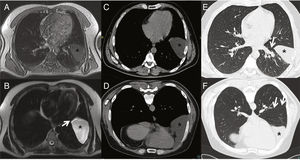

A–F) Migrating pleuropericardial cyst: A) MRI T1-enhanced axial image showing hypointense lesion (asterisk) in the left fissure. B) MRI T2-enhanced axial image showing hyperintense lesion (asterisk) in left fissure extending to pericardium (arrow). C) CT axial image obtained in supine position revealing a lesion of fluid density (asterisk). D) CT axial image obtained in prone position showing a lesion of fluid density (asterisk) with anterior shift compared to in the supine position. E) CT axial image obtained in supine position in lung window showing lesion (asterisk) in.

We decided to expand the study with computed tomography (CT) focusing on the lesion, collecting images in supine and prone decubitus. A fluid collection was observed in the left fissure when the patient was supine, in the paracardiac region when he was in right lateral decubitus, and in the anterior region in prone decubitus (Fig. 1C and F). Part of the collection remained in the cardiophrenic angle in all scans, suggesting a diagnosis of migratory pleuropericardial cyst.

Pleuropericardial cyst is a rare entity that originates from an erroneous division of the coelom, usually in the right anterior cardiophrenic angle. If the cysts are pedunculated, they can move around the chest cavity, a phenomenon known as migrating pleuropericardial cyst. Diagnosis is obtained from imaging tests when a cystic chest mass is observed that is dependent on the pericardium and changes position with the patient’s movement, appearing in the lowest regions due to the force of gravity1,2.